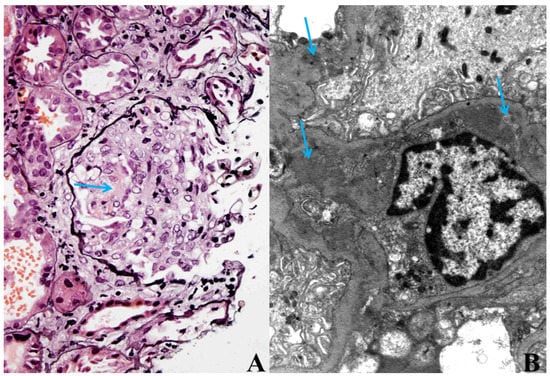

Because of the worsening of the renal function, most likely within the bacteraemia, kidney biopsy was performed. Histological analysis of the kidney biopsy showed diffuse necrotizing, crescentic, immune-mediated GN with granular deposits of IgG, IgA, IgM, C3 and C1q found predominantly in the mesangium and along the GBM. Electron microscopy confirmed this result (Figure 1A,B).

Figure 1.

(A) Cellular crescent with necrosis (arrow) in glomerulus. Jones methenamine silver staining, magnification ×400. (B) Mesangial and subendothelial immune deposits (arrows). Electron microscopy, magnification ×10,000.